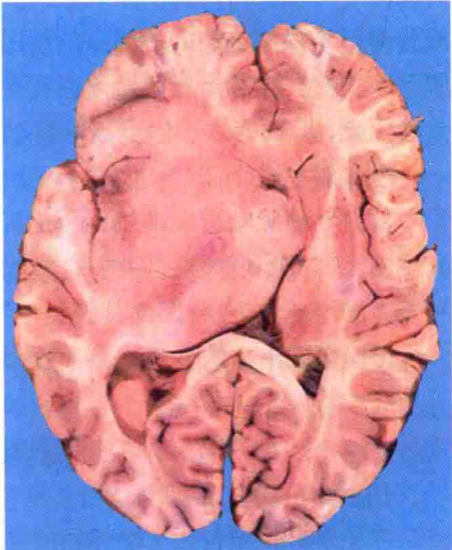

脑组织中由于液体过多贮积而形成脑水肿,这是颅内压升高的一个重要原因。许多病理过程,如缺氧、创伤、梗死、炎症、肿瘤、中毒等均可伴发脑水肿。脑水肿的肉眼形态为脑体积和重量增加,脑回宽而扁平,脑沟狭窄,白质水肿明显,脑室缩小,严重的脑水肿常同时有脑疝形成。镜下,脑组织疏松,细胞和血管周围空隙变大,白质中的变化较灰质更加明显。